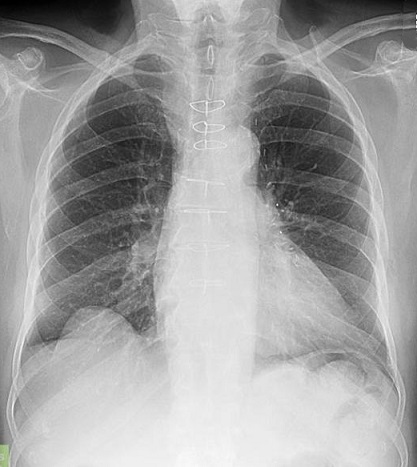

Image radiologique IRM

d'une pleuresie à moyen abondance à inferieur du

poumon droit en aspect IRM à hypointense , non

systematise, homogene situe au sinus

costo-diapragmatique latertal du poumon droit Image

IRM en coupe coronal ponderee sur T1 . |

Même cas en coupe IRM à

ponderee sur T2 . Aspect radiologique est de image

nonsystematise , homogene très hypersignal du

contenue liquidien dans espace pleurale |